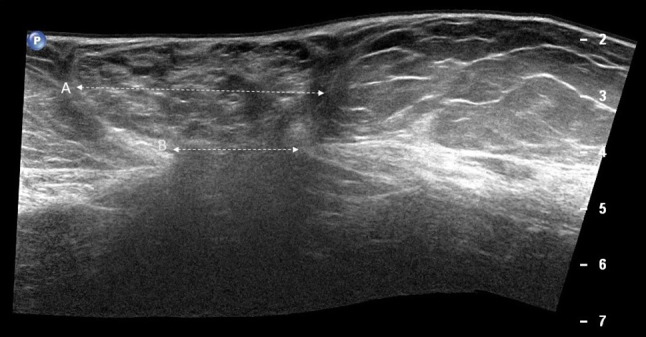

Fig. 8.

Diastasis of the rectus abdominis muscles (a, b). Diastasis of the rectus abdominis muscles is defined as an interrectus distance of 22 mm or more (a calipers), assessed three centimeters above the umbilicus. This measure must be taken in a relaxed state of the patient, avoiding traction that can make muscles to get closer to each other. b Ultrasound panoramic image. RA rectus abdominis, LA linea alba